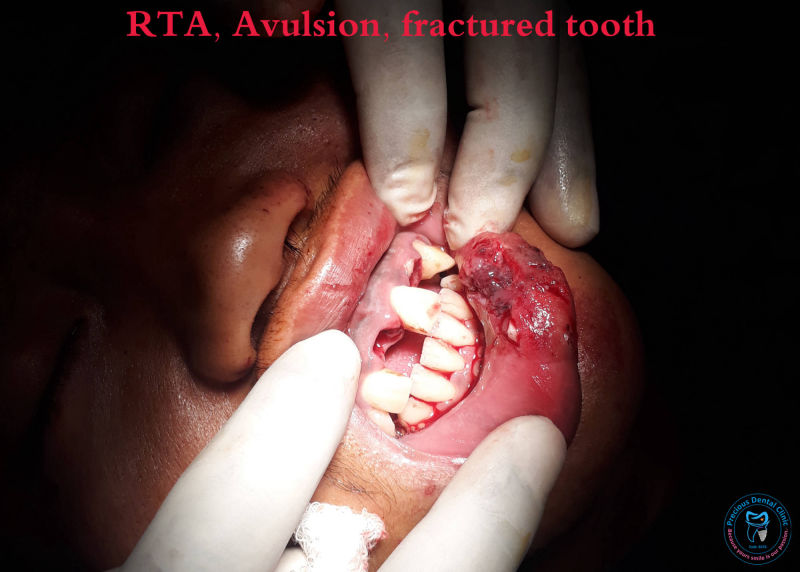

Ulcer Avulsion

Avulsion Bite Injury

Supenumery Tooth IOPAR RTA

RTA Supenumery Tooth 2